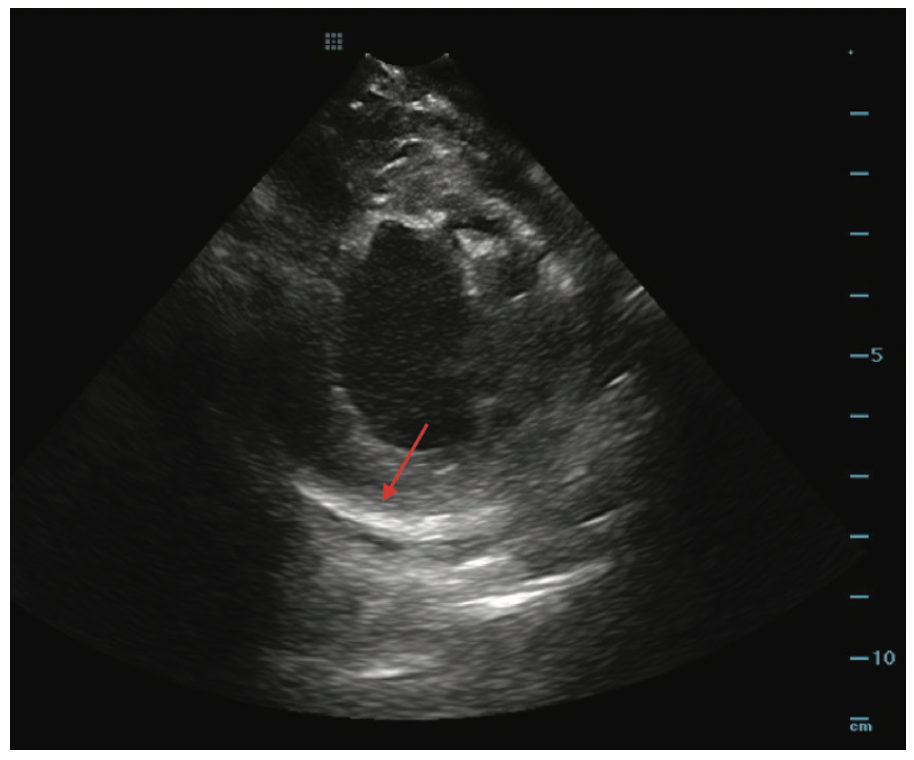

Intracardiac echocardiography (ICE) was used to visually identify areas of myocardial thinning, akinesis, and increased echogenicity, suggestive of prior infarct. In this case, ICE suggested epicardial scar in the lateral left ventricle (LV) (Figure 2).